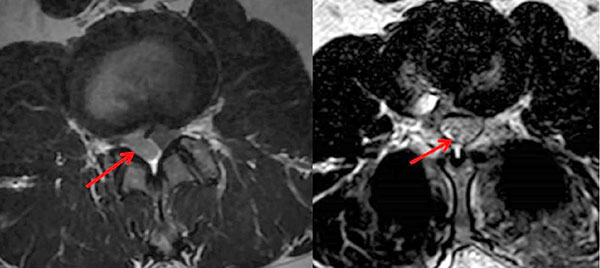

左图:术前巨大椎间盘突出压迫硬膜和神经根。右图:术后硬膜和神经根压迫解除

患者入院后得到了广东省人民医院脊柱外科医护团队的精心照料,很快完善了相关检查,确诊患者为腰椎间盘巨大突出,压迫硬膜及神经根导致下肢麻木、疼痛及乏力,患者入院时甚至出现了垂足——右下肢无法上抬,只有1-2级肌力(正常为5级)。尹东主任仔细检查患者后,认为患者目前症状严重,保守治疗已无效,右下肢肌力严重下降,并出现马尾综合征表现,需尽快手术解除神经压迫、挽救神经功能。经与患者及家属沟通及充分术前准备后,很快为患者进行了精准熟练的微创手术治疗。